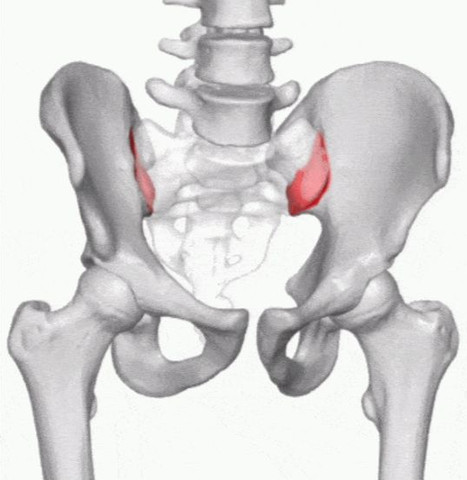

אם אתם סובלים מסיאטיקה, כאבי גב תחתון, כאבי מפרק סקרואיליאק,

חייבים להכיר את חגורת הגב המקלה על פריצת דיסק / בלט דיסק - כאבי גב חזקים והקרנות לכפות רגליים, לאגן ולישבן.

*מיקום החגורה- מקם את הרצועה בצורה נכונה: מקמו את החגורה סביב המפרק על ידי בדיקת הקמט בעת הרמת אחת מהרגליים

ודא כי הרצועה צמודה, החגורה צריכה להיות צמודה לגוף אך לא הדוקה מדי, היא לא אמורה להגביר את הכאב שלך.